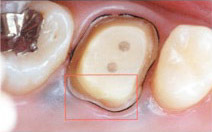

う蝕検知液とは、虫歯の部分のみを赤く染める薬剤です。

虫歯治療を行う上で一番大切なのは、虫歯に感染した部分を完全に除去することですが、通常は虫歯の硬さを頼りに、軟らかくなった部分を削っていきます。

しかし、この方法では、感染部位を確実に、そして正確に除去することはできません。

しかし、このう蝕検知液を使うと、感染した部分が赤く染まりますので、どこまで虫歯を削ればよいかがわかり、歯を削る量を最小限に抑えることができます。